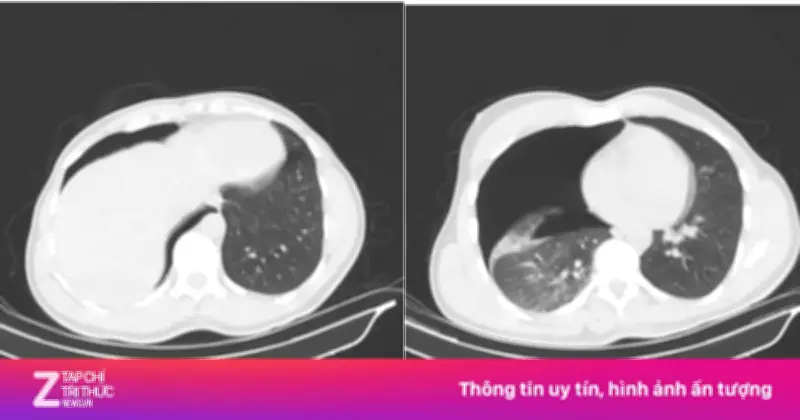

Kết quả chụp CT scan lồng ngực - mạch máu cho thấy bệnh nhân bị tràn khí màng phổi phải lượng nhiều, chèn ép phổi gây khó thở. Ngoài ra, anh còn bị gãy cung bên các xương sườn số 2, 3, 4 bên phải và gãy phức tạp 1/3 giữa xương đòn phải với di lệch nhiều và có mảnh rời.

Bác sĩ Phạm Ngọc Huy, khoa Điều trị theo yêu cầu - Y học thể thao, nhấn mạnh: "Nếu không can thiệp kịp thời, tình trạng suy hô hấp có thể diễn tiến nguy hiểm". Khoảng 5h sáng cùng ngày, ê-kíp khoa Phẫu thuật Tim - Lồng ngực - Mạch máu đã tiến hành đặt dẫn lưu màng phổi phải cấp cứu. Thủ thuật được thực hiện nhanh chóng và chính xác, giúp phổi nở trở lại tốt. Chỉ sau vài giờ, tình trạng hô hấp của bệnh nhân đã cải thiện rõ rệt.